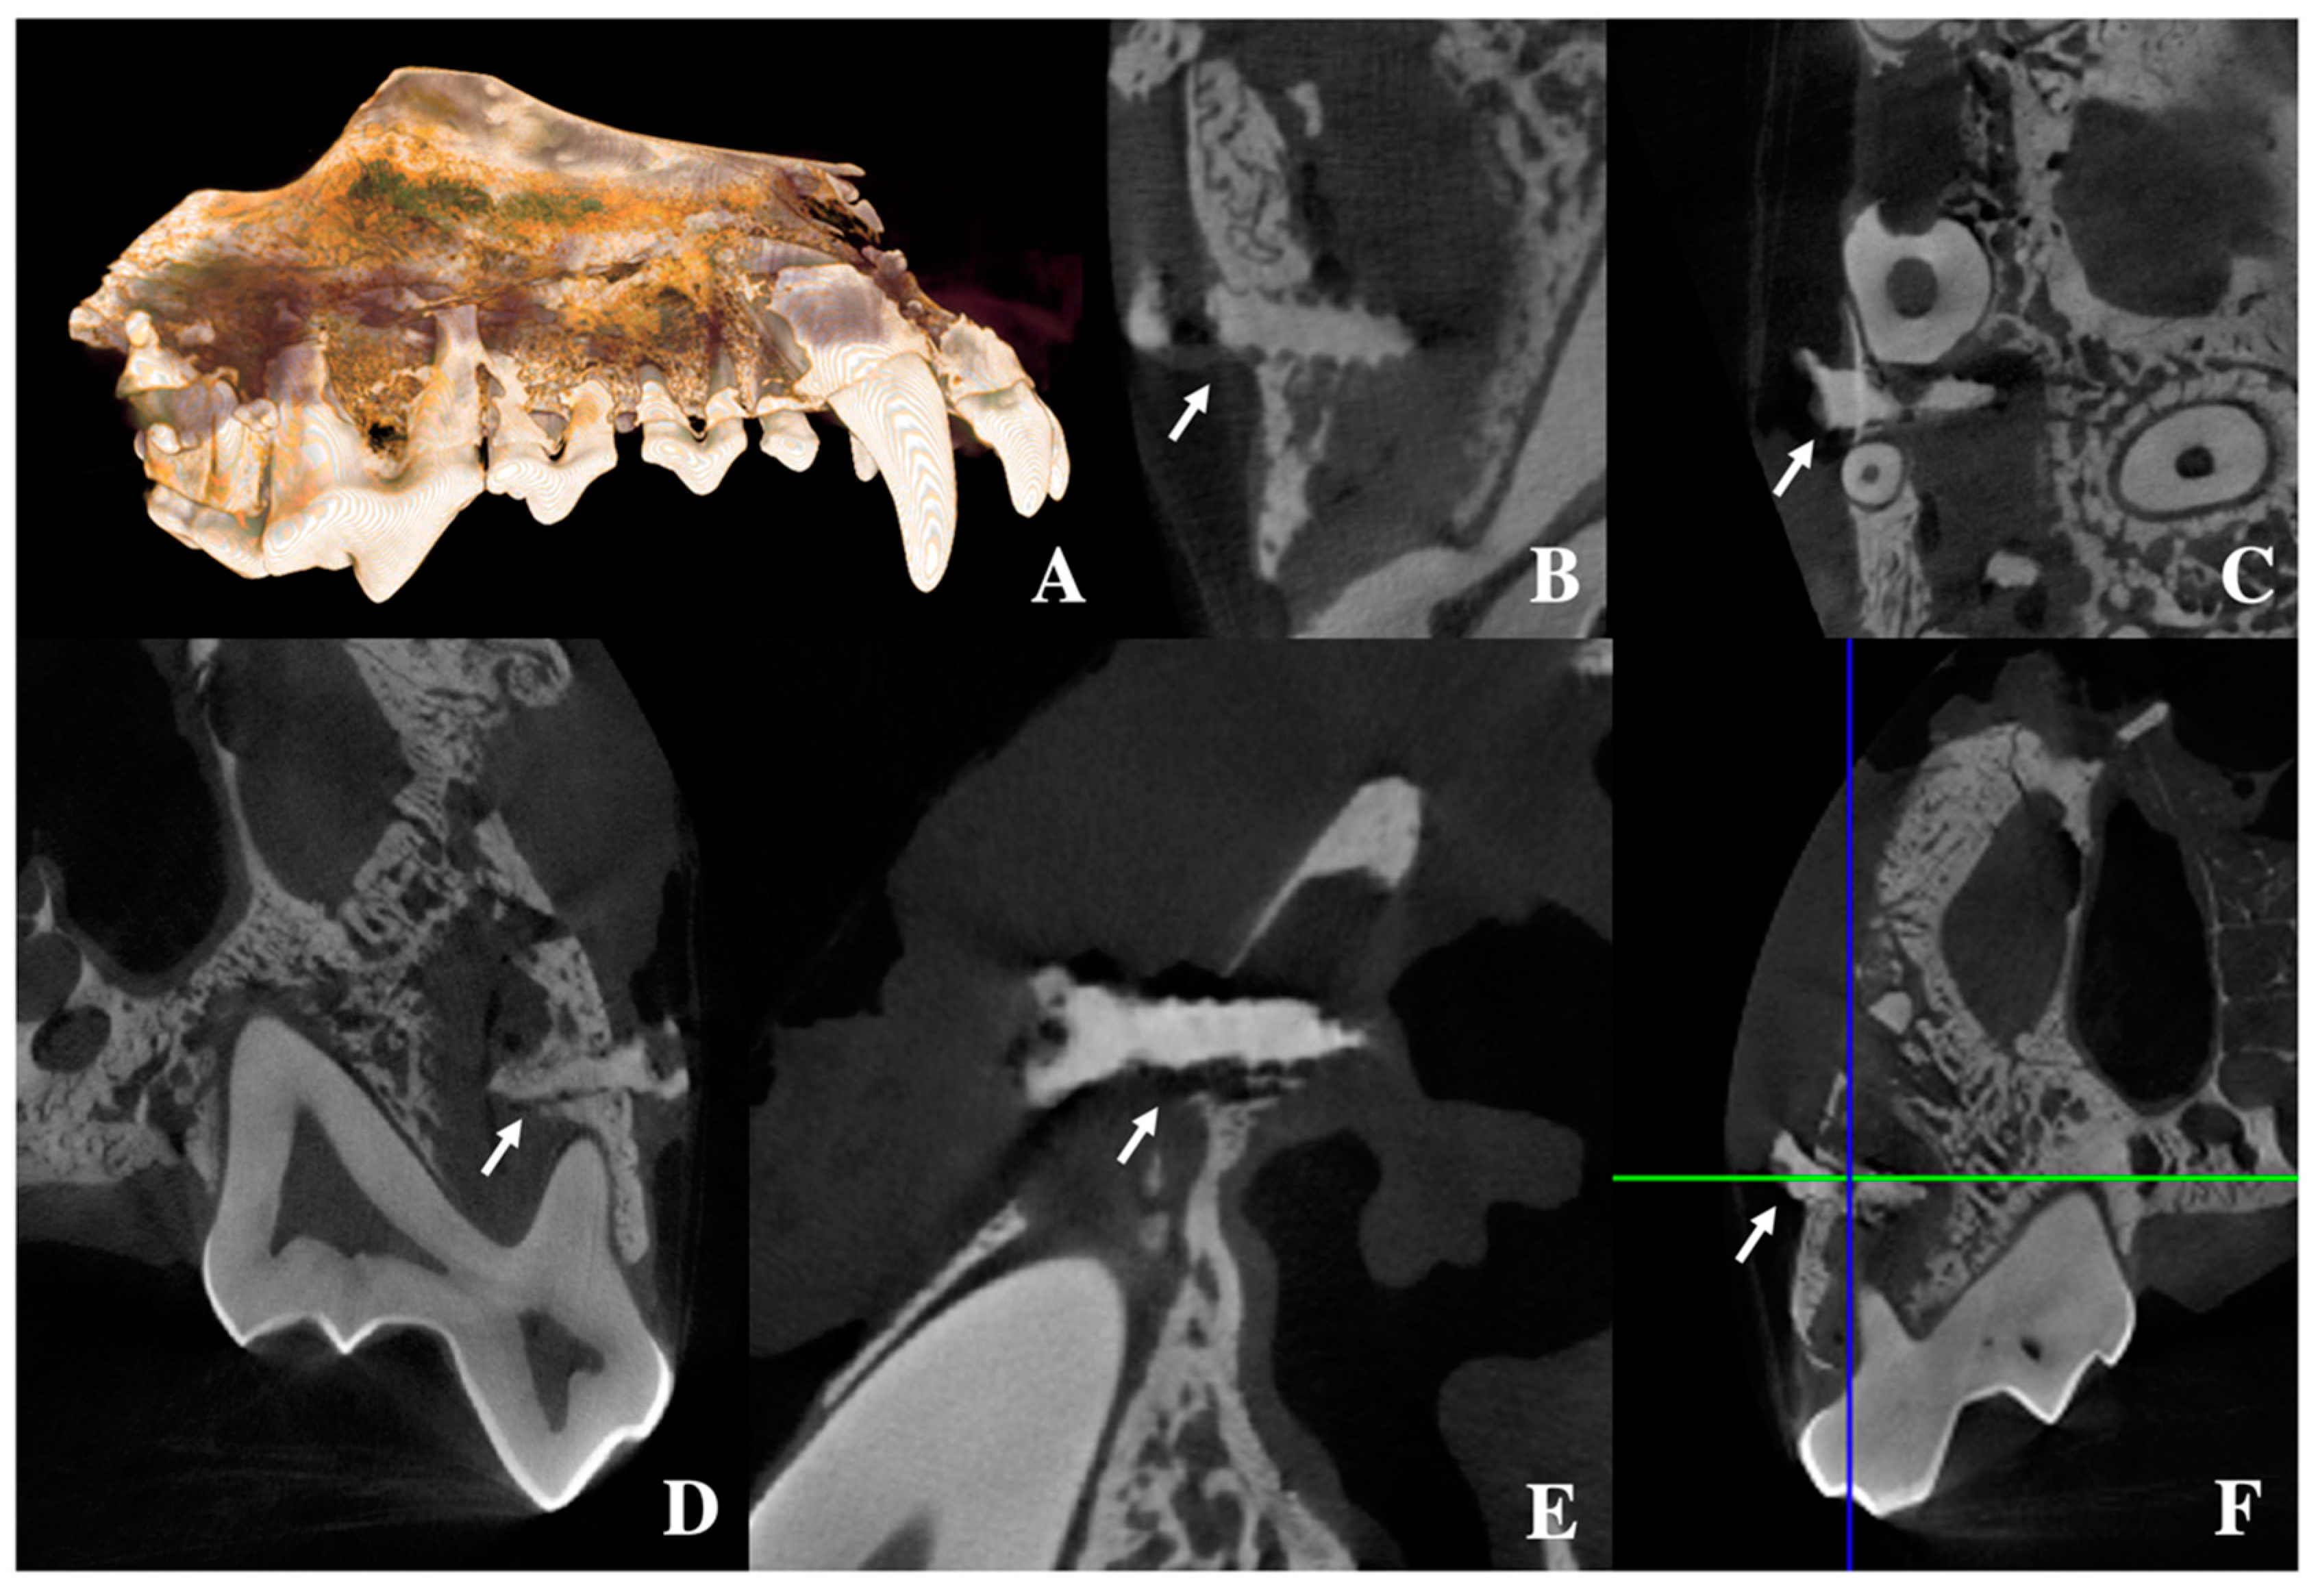

3.4. Evaluation of PLLA-Coated ZK60 Plate Using a LeFort I Osteotomy Canine Model

3.4.1. Clinical Evaluation

3.4.2. Evaluation of Absorption Rate Using µCT